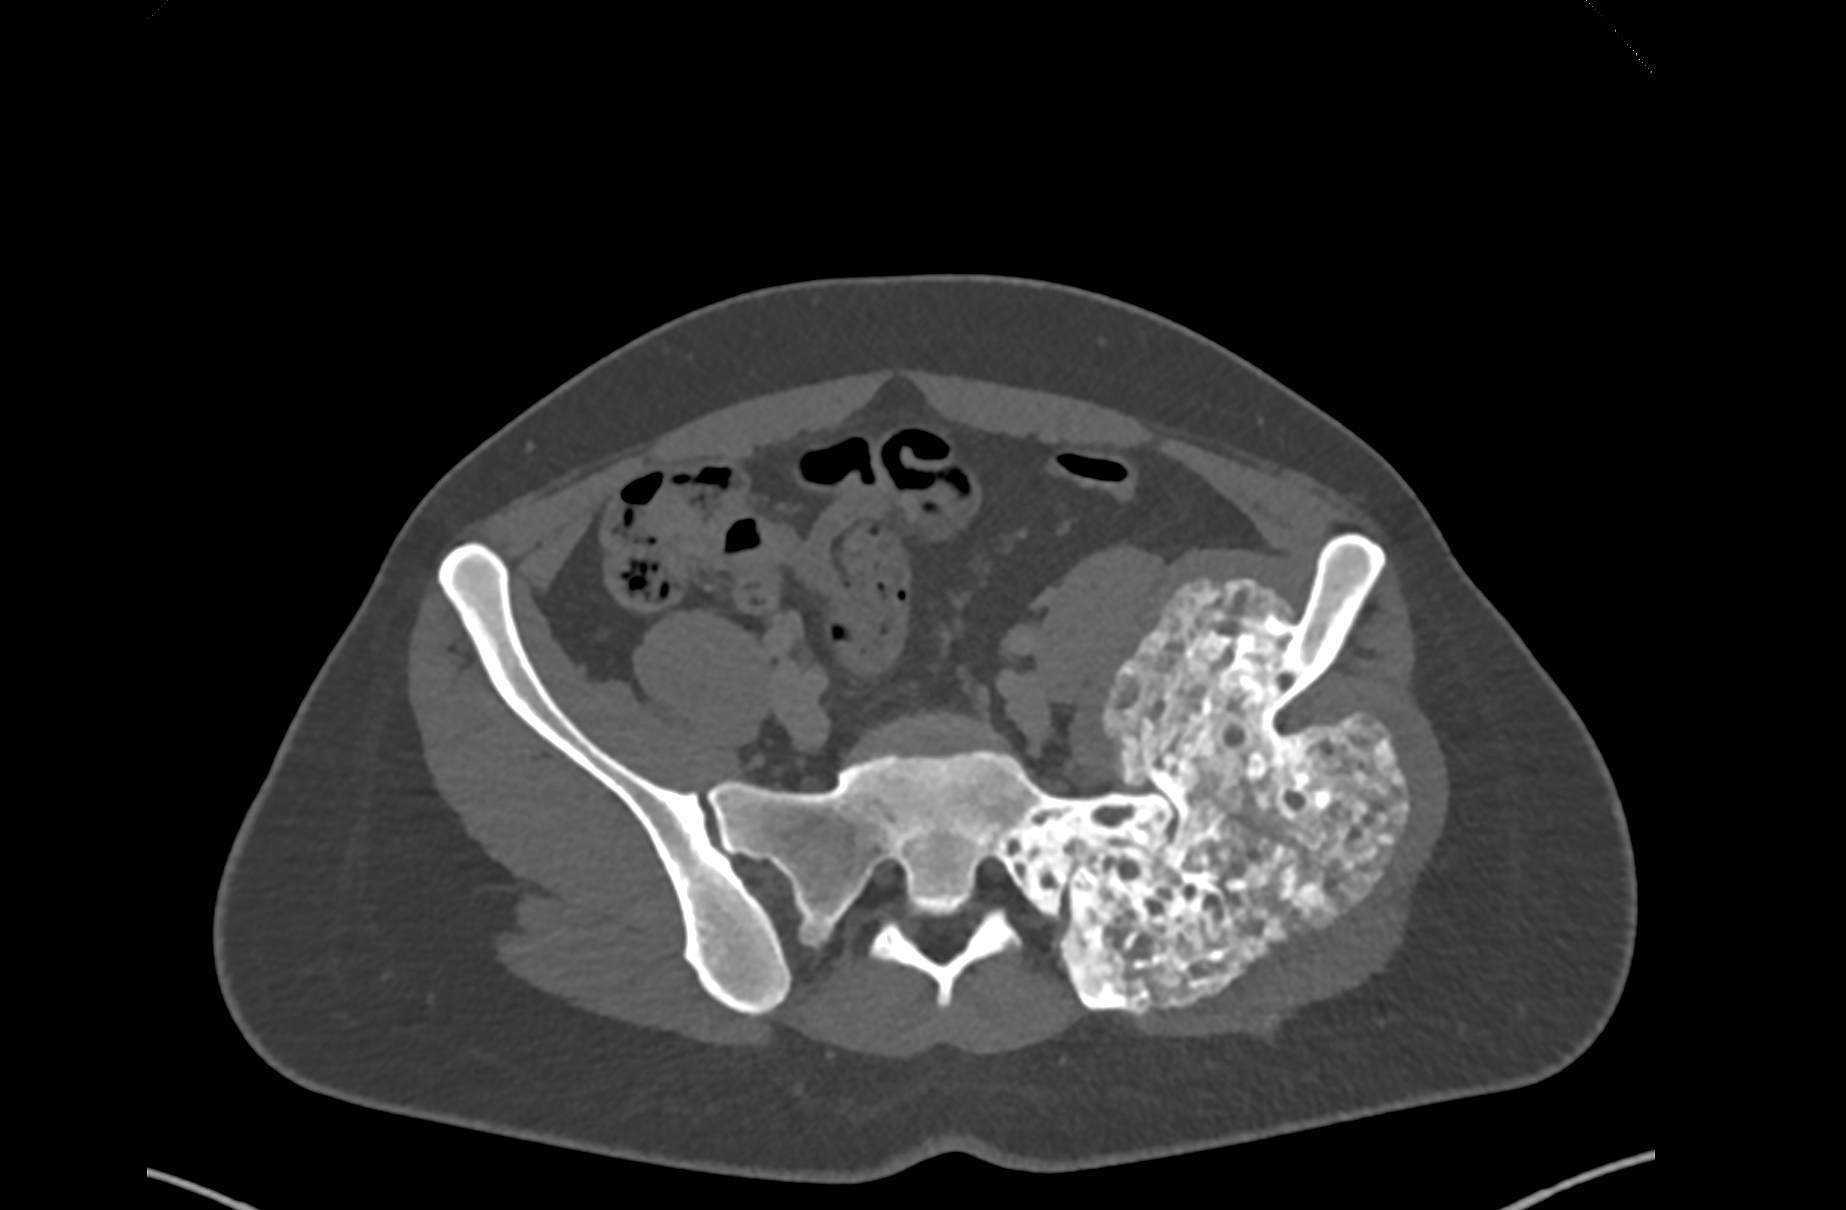

A 27-year-old female patient presented with a giant cell tumor of the left iliac wing that extended into the sacrum. After one year of neoadjuvant DENOSUMAB therapy,

surgical removal was indicated. Since the acetabulum was tumor-free, the hip joint could be preserved. The surgical objective was to achieve wide resection margins

Figure 2: Preoperative MRI showing tumor extension into the sacrum with a preserved acetabulum.